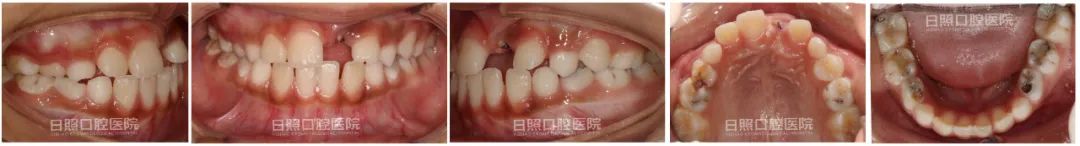

治疗前口内照

手术开窗和正畸牵引的工作做完以后,就是等待牙齿逐渐萌出,接下来的几张图片就是2.5个月、5个月、7个月、10个月直到矫治后的图片,大家一起来见证一下”奇迹“吧!